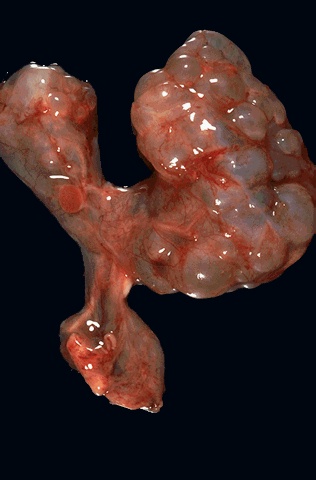

Image 1.7 The gross appearance of multicystic renal dysplasia is seen here. Note the asymmetry of the kidneys.